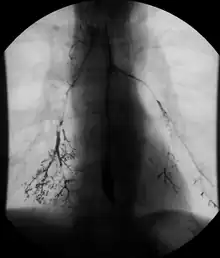

Enteroclysis

Enteroclysis is also known as small bowel enema.[21] It has been largely replaced by magnetic resonance enterography/enteroclysis[13] and computed tomography enterography/enteroclysis.[22]

In addition to fasting for 8 hours prior to examination, a laxative may also be necessary for bowel preparation and cleansing.[12] The main aim of this study is to distend the proximal bowel through infusion of large amount of barium suspension. Otherwise, the distension of distal small bowel is generally similar with small bowel follow-through. Therefore, there is a need to pass a tube through the nose into the jejunum (nasojejunal tube) to administer large amount of contrast. This can be unpleasant to the subject, requires more staff, longer procedural time, and higher radiation dose when compared to small bowel follow-through. The indications for enteroclysis are generally similar to small bowel follow-through. Barium suspensions such as diluted E-Z Paque 70% and Baritop 100% can be used. After that, 600 ml of 0.5% methylcellulose is administered after 500 ml of 70% barium suspension is given. Bilbao-Dotter tube and Silk tube can be used to administer barium suspension. The subject should be fasted overnight, any antispasmodic drugs should be stopped one day before the examination, and Tetracaine lozenges can be used 30 minutes before the procedure to numb the throat for nasojejunal tube insertion.[13]

The filling of the small intestines can be viewed continuously using fluoroscopy, or viewed as standard radiographs taken at frequent intervals. The technique is a double-contrast procedure that allows detailed imaging of the entire small intestine. However, the procedure may take 6 hours or longer to complete and is quite uncomfortable to undergo.[23]